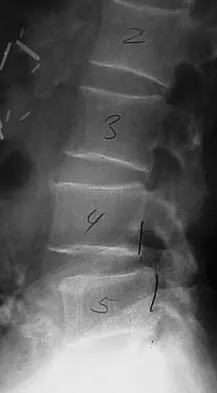

An otherwise healthy 70-year-old man has back and bilateral leg pain in an L5 distribution that is aggravated by standing more than 10 minutes or walking more than 100 feet. He has to sit to get relief. Neurologic and pulse examinations are normal. A radiograph and MRI scan are shown in Figures 4a and 4b. Treatment should consist of

The patient has a degenerative spondylolisthesis at L4-5 with associated spinal stenosis. His symptoms are consistent with neurogenic claudication. Based on these findings, the surgical treatment of choice is decompression and posterolateral fusion. Use of instrumentation is controversial. Laminectomy alone is reserved for the patient who is frail medically. There is no role for an anterior approach or for fusion alone without decompression. Fischgrund JS, Mackay M, Herkowitz HN, et al: Degenerative lumbar spondylolisthesis with spinal stenosis: A prospective, randomized study comparing decompressive laminectomy and arthrodesis with and without spinal instrumentation. Spine 1997;22:2807-2812.